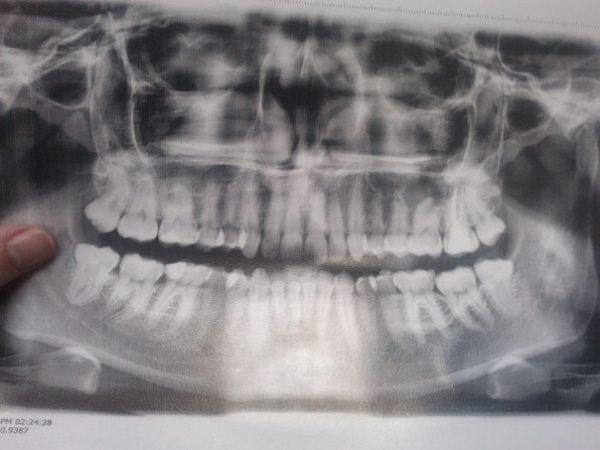

Год назад у меня отломился кусочек зуба - шестерка снизу. Оказался кариес, походила с временной пломбой, удалось сохранить нерв, запломбировали и год проблемы не знала. Как-то ночью проснулась от зубной боли, естественно, ни полоскания содой, солью, йодом - ничего не помогало, обезболивающее тоже не брало. Помогала холодная вода - за щеку и легчало. Опухла десна, я подумала, что это зуб мудрости так лезет (у меня все четыре вылезли, а этот, восьмерка, периодически начинает прорезаться, но не доставляет боли, но я подумала на него). До этого, две недели назад, была у врача, сказал все отлично, и на тебе. Я терпела два дня, сходила, сделала панорамный снимок, чтобы посмотреть, как растет зуб мудрости - дергать или нет. На снимке все удачно оказалось (я не сторонница выдирания зубов). Пришла к врачу со снимком, посмотрел, увидел отек десны - сказал, что это та шестерка - пульпит. Почистил каналы, положил лекарство, поставил временную пломбу. Два дня болело, но думала нормальная реакция на постороннее вмешательство. Боли были: ныло, при надавливании болело. Через пять дней пошла к врачу (временную пломбу положил на 14 дней). Посмотрел, сказал вскрывать смысла нет, т. к. все нормально. Сегодня десятый день. Два дня без обезболивающего, не ноет зуб, но теперь мне больно открыть широко рот - будто чувствую все корни этого зуба, он пульсирует, и вокруг этого зуба и соседних - краснота. Неприятных запахов нет, гноя нет, никаких приростов тоже нет. К врачу через три дня. Боюсь самого страшного, что плохо вылечил, и могу теперь потерять зуб. Хотелось бы узнать ваше мнение.

Что может быть с зубом, и в случае, если назначат удаление, я обязана платить за это? С самого начала лечения, год назад и до настоящего момента - все манипуляции производил один врач.

Ничего удалять не нужно, смените доктора и обратитесь к более грамотному специалисту. На снимке я не вижу следов качественного лечения, каналы либо пустые, либо залиты резорцин-формалиновой пастой, чего делать нельзя.